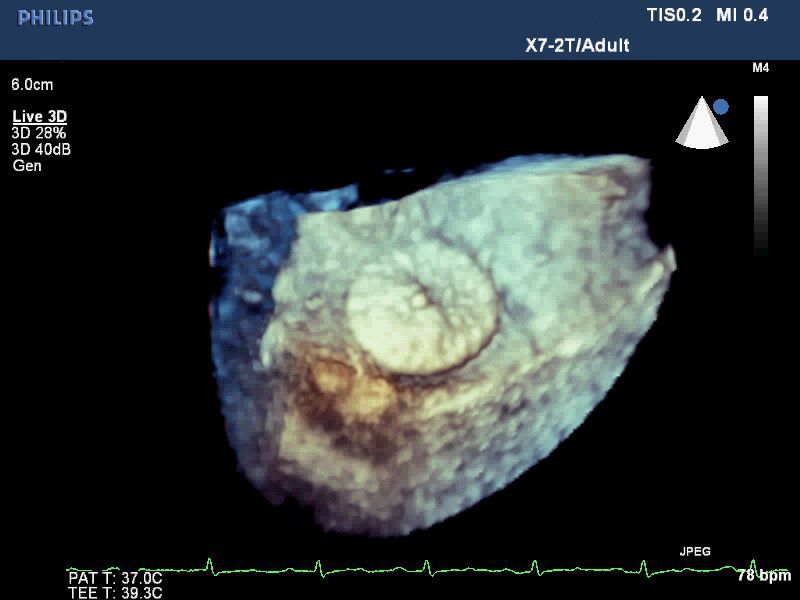

• 3D-эхокардиография в реальном времени с углубленным количественным анализом

• Улучшенная визуализация с помощью матричных датчиков при проведении 3D-эхокардиографии

• Live 3D Echo: Эта функция позволяет получать объемные 3D-изображения анатомии и механики сердца в режиме реального времени, расширяя возможности эхокардиографии.

• 3D эхо-кг в реальном времени (Live3DEcho): Эта технология позволяет получать объемные 3D изображения сердца в режиме реального времени.